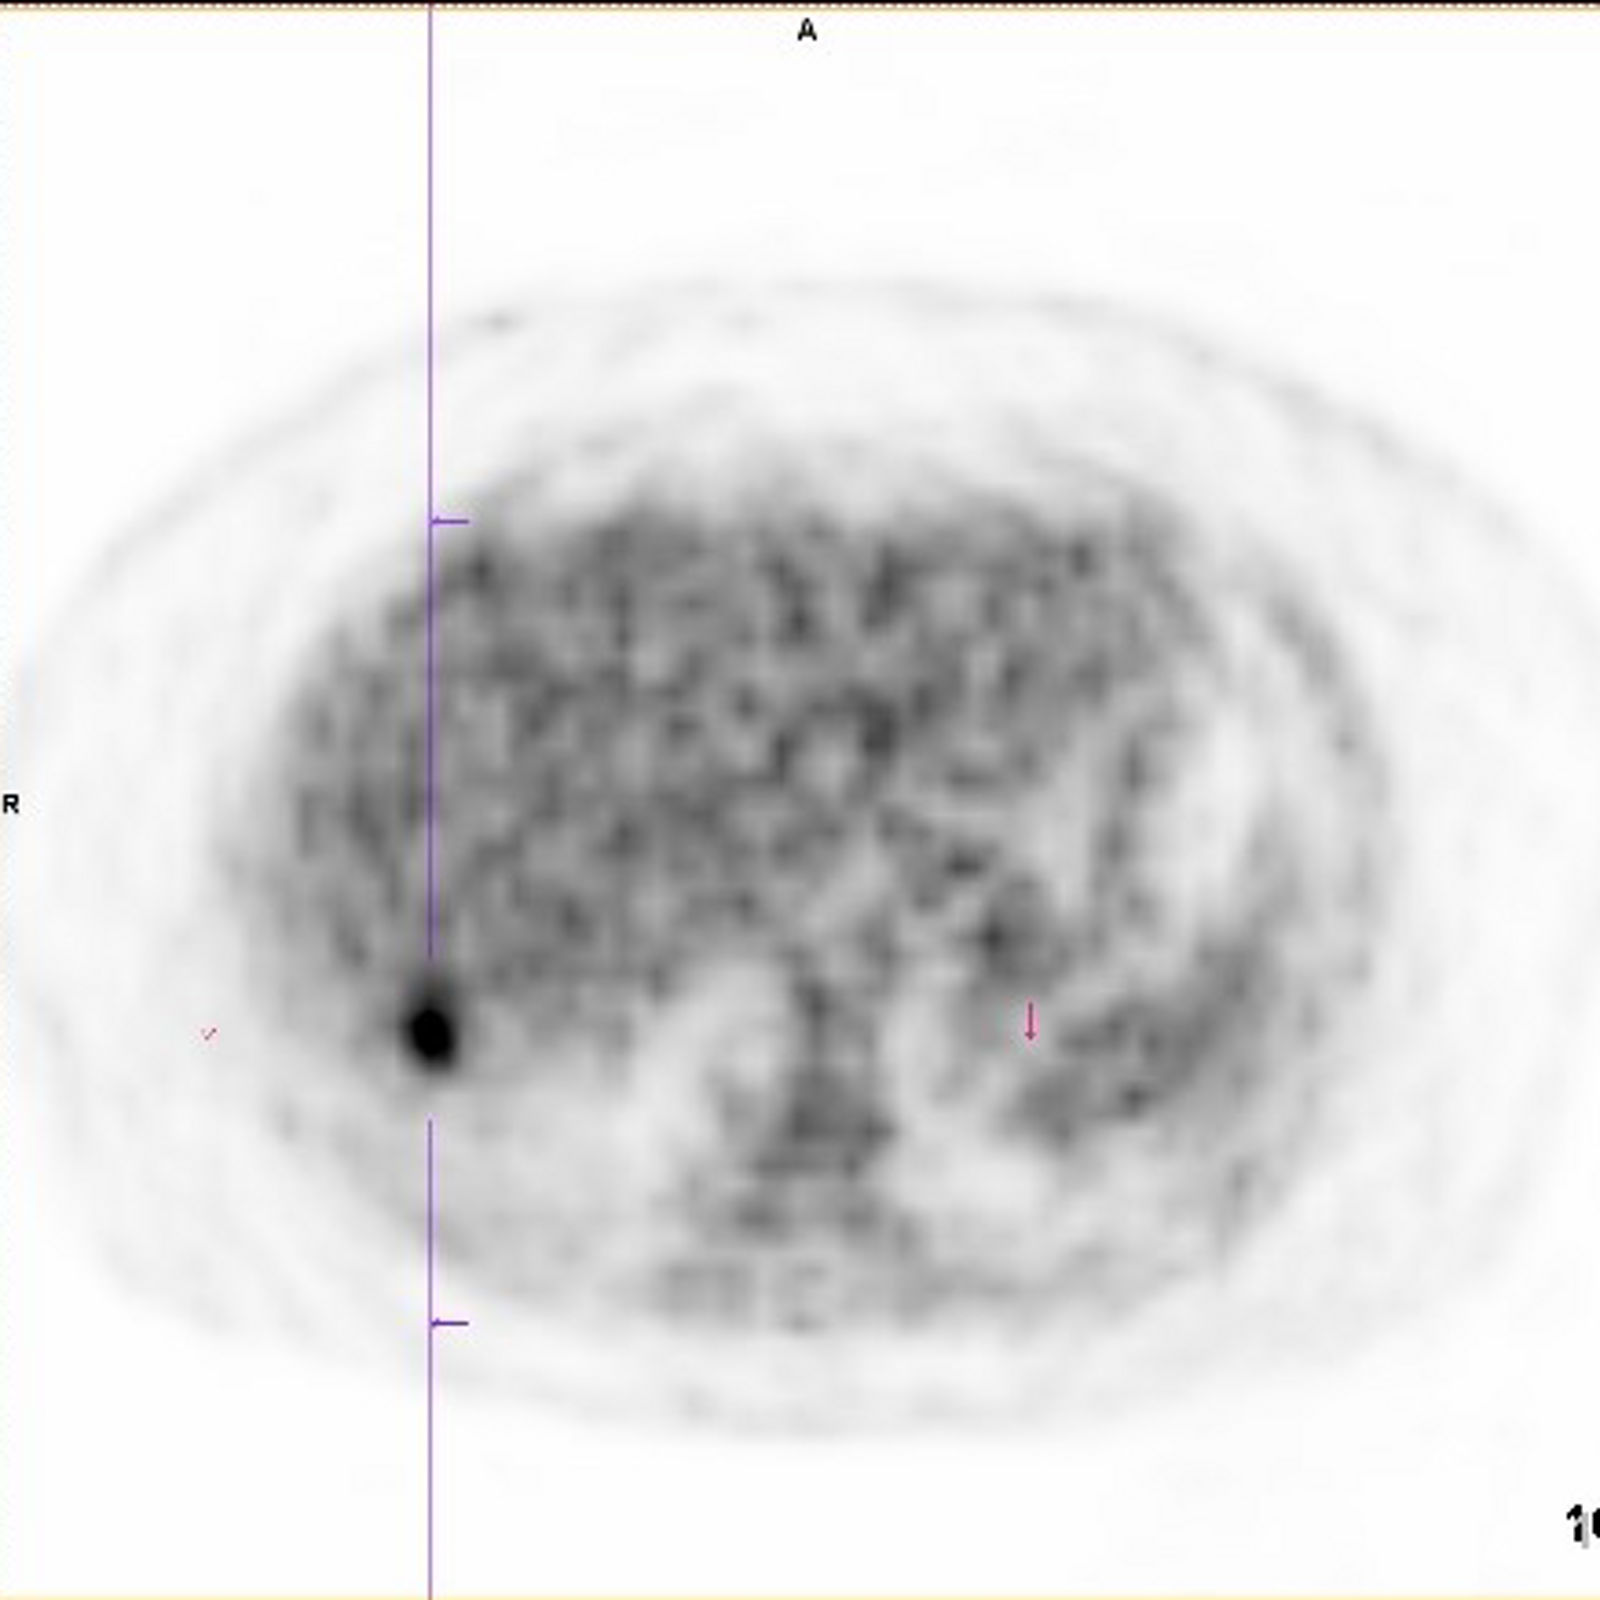

Die PET-CT-Untersuchung ist eine kombinierte nuklearmedizinisch-radiologische Bildgebung, eine Positronenemissionstomographie kombiniert mit Computertomographie. Sie stellt auf der einen Seite Stoffwechselveränderungen dar, auf der anderen Seite morphologische Veränderungen.

Meist wird mit F-18 markierte Glukose verwendet, um die Verteilung des Glukosestoffwechsels darzustellen, es können aber auch z.B. Rezeptor gerichtete Substanzen verwendet werden. Im CT-Teil der Untersuchung werden die morphologischen Verhältnisse dargestellt, je nach Fragestellung und Vorbefunden mit diagnostischer CT oder als Niedrig-Dosis-CT.

Kolorektale Karzinome haben in der Regel einen deutlich gesteigerten Glukosestoffwechsel, d.h. sie können in der PET-CT durch eine vermehrte Speicherung des verwendeten Radiopharmakons nachgewiesen werden. Auch Metastasen eines kolorektalen Karzinoms weisen diesen erhöhten Glukosestoffwechsel auf.

Die Frage nach Lungenmetastasen oder anderen Fernmetastasen kann in der Rezidivdiagnostik mit der PET-CT beantwortet werden. Auch ist die Klärung eines möglichen präsakralen Rezidivs in Abgrenzung zu einer präsakralen Narbenplatte in der konventionellen Schnittbildgebung nicht immer möglich. Hier kann die PET-CT einen erhöhten Glukosestoffwechsel bestätigen oder ausschließen.

In der Beurteilung möglicher Fernmetastasen kann die PET-CT wertvolle Zusatzinformationen liefern, die die primäre Therapie beeinflussen können, z.B. bei der Beurteilung von Lungenrundherden unklarer Dignität, die Lungenmetastasen entsprechen oder aber auch Zweitmalignomen oder narbigen Veränderungen entsprechen könnten.

Auch kann vor Resektion von resektablen Lebermetastasen die PET-CT mit dem Ziel der Vermeidung einer unnötigen Laparotomie durchgeführt werden. (S3-Leitlinie Kolorektales Karzinom)